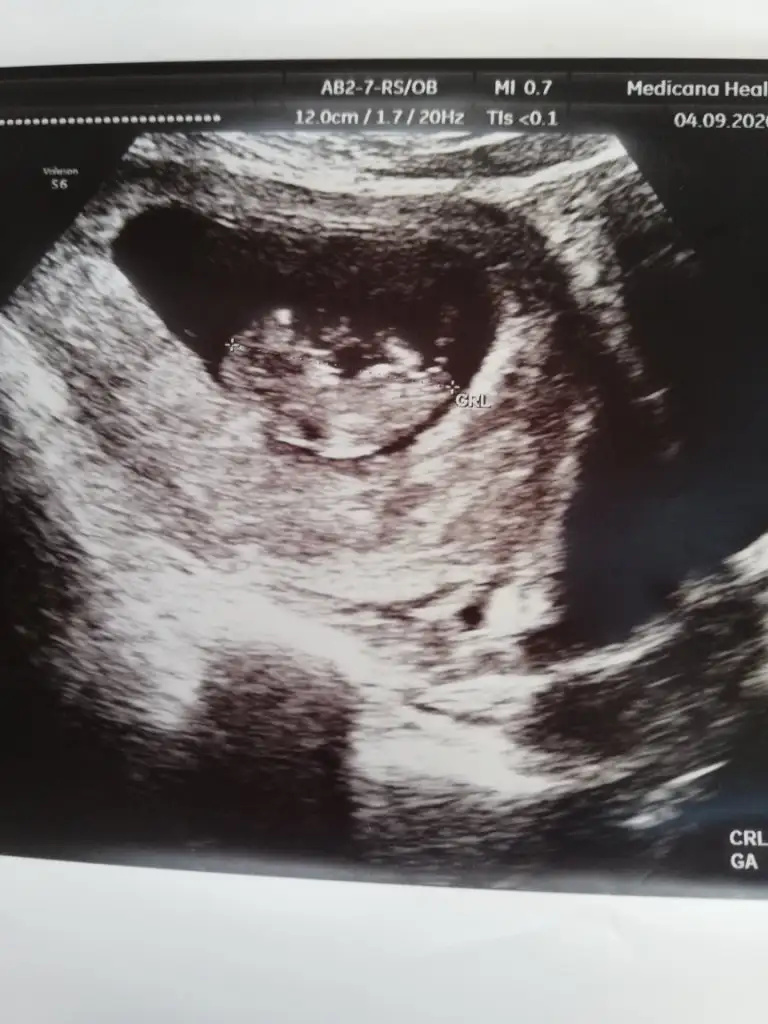

Teyzeler biz de bugün dr gittik. Şükür herşey yolundaymış. 2 hafta sonra ikili teste gelirsin cinsiyet söylerim dedi.. Kızım da ilk defa kontrole geldi benimle çok heyecanlıydık.Doktor amcamız kızımın da doktoru ilk defa gördü büyümüş halde çok mutlu oldu.. Size de selam verelim dedik.

Teyzeler biz de bugün dr gittik. Şükür herşey yolundaymış. 2 hafta sonra ikili teste gelirsin cinsiyet söylerim dedi.. Kızım da ilk defa kontrole geldi benimle çok heyecanlıydık.Doktor amcamız kızımın da doktoru ilk defa gördü büyümüş halde çok mutlu oldu.. Size de selam verelim dedik.Eki Görüntüle 2685224 Eki Görüntüle 2685224

Maşallah kaç haftalık canım 😊 baya büyümüş minnoş